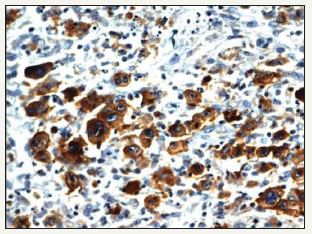

Composite lymphoma as an entity was initially described by Custer et al followed by a modified delineation by Hicks et al and Kim et al with a categorical emergence of architecturally diverse and binary cytological subcategories of lymphoma within the same anatomic site or tissue. Composite lymphoma as a disorder essentially describes a biphasic elucidation of an identical malignant clone of cells [1]. A discordant lymphoma may be exemplified by a condition in which two disparate lymphomas may arise at different anatomic locations within an identical time frame (Figure 1). Sequential lymphoma may be characterized by the appearance of two distinctive histological variants of malignant lymphoma detected successively within a similar group of lymph nodes.

Figure 1:CL: small and large B cell zones with cellular pleomorphism [13].